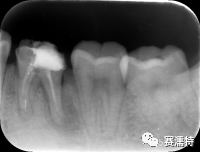

張凈玉老師案例